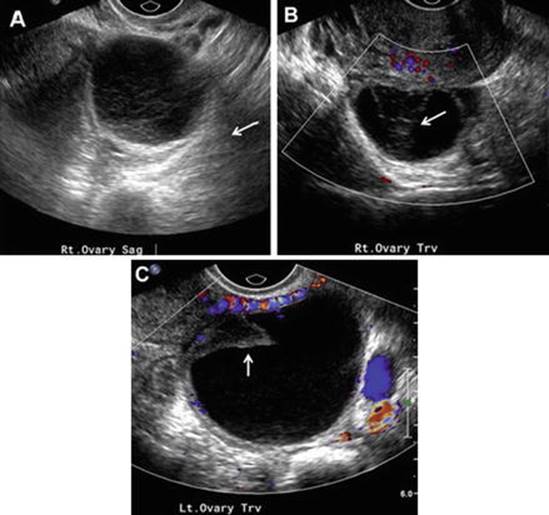

Hemorrhagic Cyst

By ultrasound, hemorrhagic cysts may have fluid-fluid levels, internal echoes, and/or a mural thrombus; these cysts usually have circumferential flow without internal color Doppler flow (Fig. 4.4) [51, 54]. An internal reticular and lacy pattern due to fibrin may be noted, but do not cross the whole cyst, unlike septations [6]. The sonographic appearance of a hemorrhagic cyst may mimic that of an endometrioma, or vice versa. In premenopausal women, hemorrhagic cysts are expected to resolve and can be followed with a repeat ultrasound in 6–8 weeks to ensure resolution. Conversely, a cyst which appears hemorrhagic in a postmenopausal woman is potentially concerning for neoplasia and require close follow-up, as ovulation is no longer occurring in these women [54].

Fig. 4.4

Hemorrhagic ovarian cysts. (a) Transvaginal ultrasound demonstrates a thin-walled hypoechoic cyst with a “lacelike” pattern of internal low-level echoes representing fibrin formation from lysis of RBCs (arrow). (b, c) Transvaginal ultrasound demonstrating a later stage of hemorrhagic cysts, which contain retractile clot seen as heterogeneous iso-echoic to hypoechoic irregular-shaped mural foci (arrows) without Doppler flow (Reprinted from Amirbekian and Hooley [51], with permission from Elsevier)